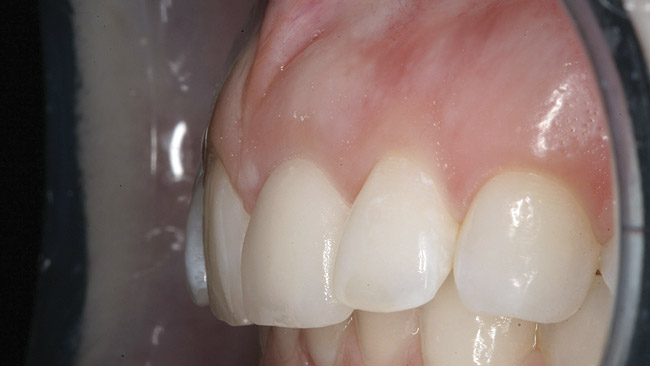

Figure 3  Shade selection for final crowns, teeth Nos. 22 through 28; post-extraction of No. 26 and decoronation of Nos. 24 and 25; Nos. 22, 23, 27, and 28 prepared for full coverage.

Figure 3

The final treatment plan called for replacement of teeth Nos. 24 through 26 with implants, and four adjacent porcelain crowns. The restorative dentist prepared these four teeth for full coverage and decoronated Nos. 24 and 25, then, with patient input, selected a shade (Figure 3) and fabricated a bis-acryl temporary bridge from Nos. 22 to 28. After extracting teeth Nos. 24 and 25, the periodontist performed socket preservation in addition to horizontal ridge augmentation in site No. 26 with FDBA and a resorbable porcine collagen membrane. The flaps were approximated with 4-0 polyglactin 910 (Figure 4). Figure 5 shows the 7-unit bis-acryl temporary bridge.